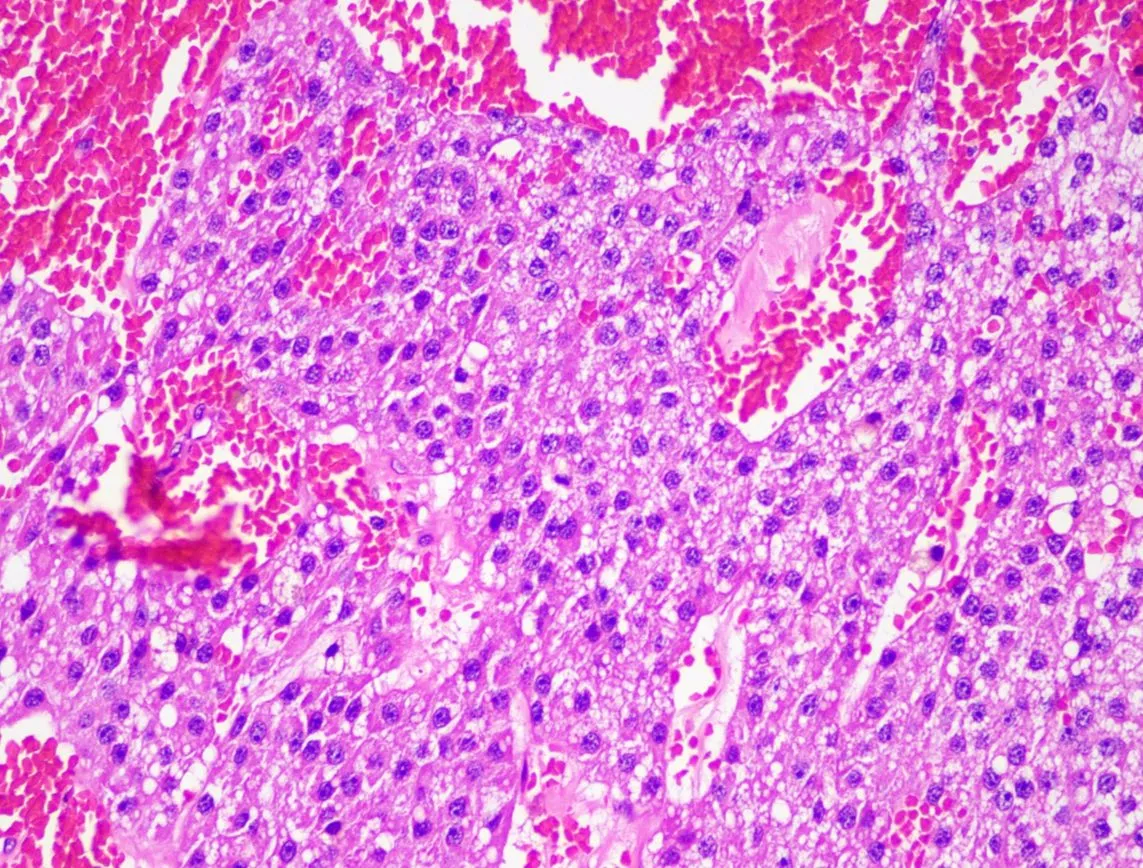

🐾 最後分享一個病例,這隻14歲的狗狗因為睪丸越來越大,快要垂到地上來就診,檢查之下不僅左邊睪丸變成腫瘤,右邊居然也有隱睪! 手術還不得不連陰囊也一起切除了(正常絕育時不需切除),切片結果是有轉移風險的惡性腫瘤,塞托利細胞瘤(Sertoli cell tumor),術後還需要持續觀察!

🐾 最後分享一個病例,這隻14歲的狗狗因為睪丸越來越大,快要垂到地上來就診,檢查之下不僅左邊睪丸變成腫瘤,右邊居然也有隱睪! 手術還不得不連陰囊也一起切除了(正常絕育時不需切除),切片結果是有轉移風險的惡性腫瘤,塞托利細胞瘤(Sertoli cell tumor),術後還需要持續觀察!